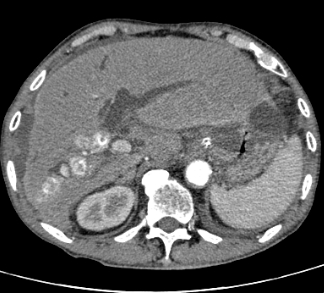

术前CT影像

患者为80岁男性,因右上腹剧痛、发热伴恶心呕吐入院,完善检查后确诊为急性化脓性胆管炎,其病因在于右肝内胆管、胆囊及胆总管内广泛性结石继发肝内外胆道感染,病情危急,需尽早手术治疗。但患者60余年的吸烟史及需右半肝切除的上腹部手术极大地增加了围手术麻醉、手术和术后的康复风险。